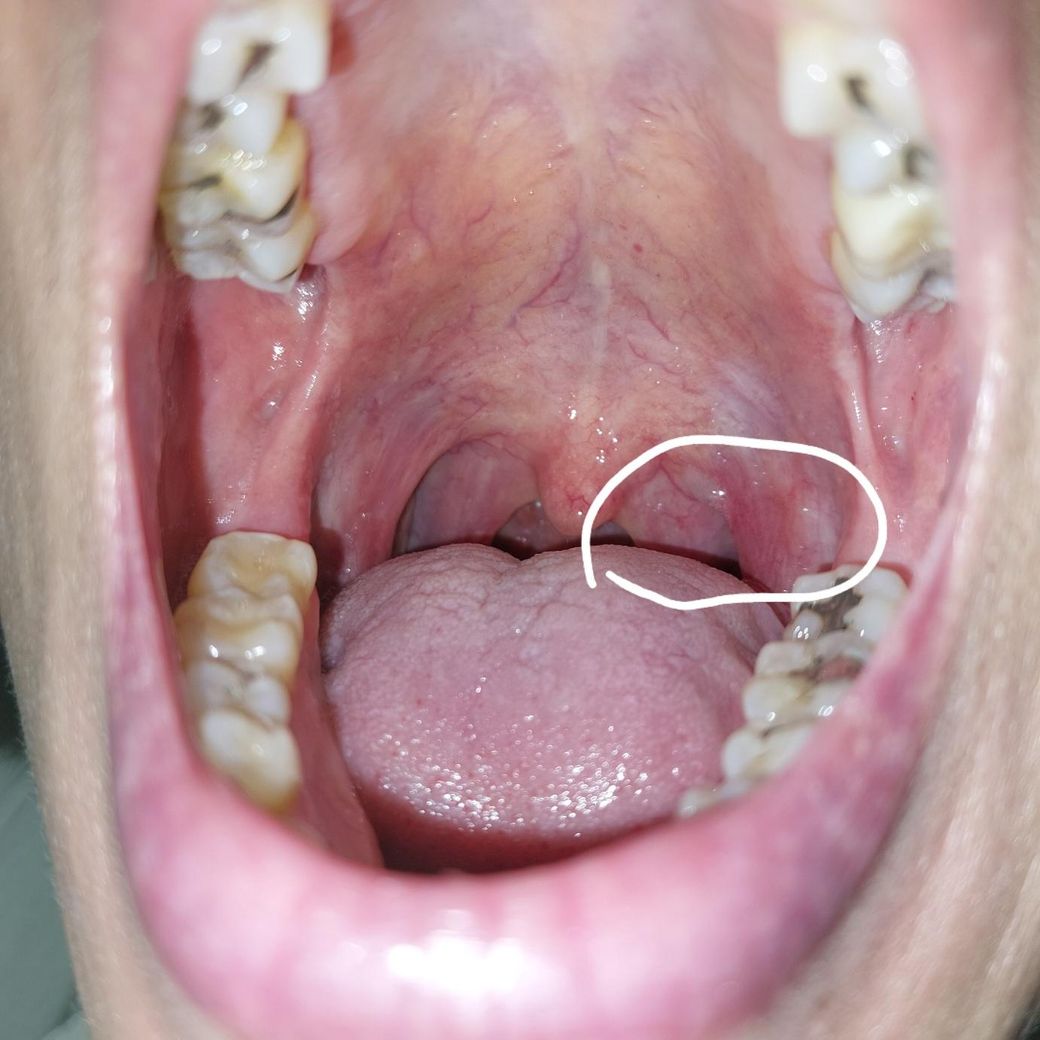

목안이 헐은것처럼 아픈데 하얗게 생긴 저거 뭘까요?

5ㅡ6개월전부터 목이 헐은것처럼 아팠는데 오늘도 아파서 사진을 찍었더니 하얗게 부푼 느낌으로 보이더라고요

혹시니 해서 동네 소아과 갔는데 어디가 이상하다는건지.모르시겠다며ㅠㅠ

근데ㅡ저는 목구멍이.아파요ㅠㅠ

• 1번 째 사진

올려주신 사진에서 특별한 이상소견은 관찰되지 않습니다.

불편 증상이 지속된다면 직접 진찰을 위해 이비인흔과 진료를 받아보실 것을 권합니다.

음주, 흡연, 자극적인 음식의 섭취는 인후통을 악화시킬 수 있어 피하기 바랍니다.